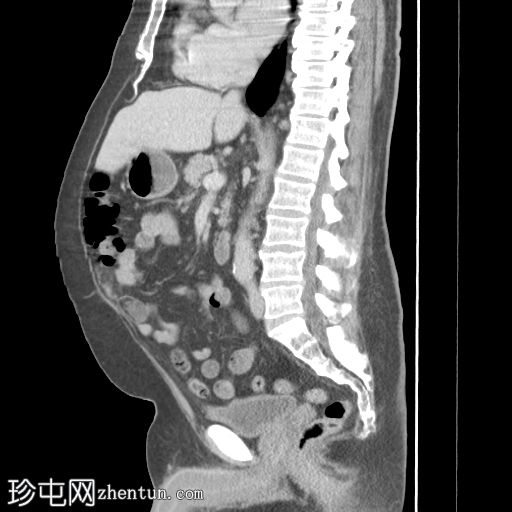

冠状位增强扫描(门静脉期)

肾周可见重度、相对均匀的浸润,呈“毛肾征”。肾积水,但无输尿管积水。

肝、脾、胰腺和肾上腺正常。胆囊正常,无胆管扩张。